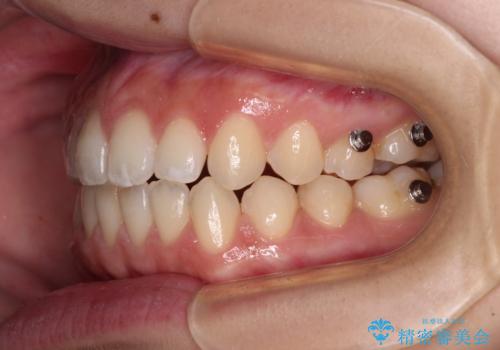

- 上下前歯の隙間と咬み合わない前歯を気にして来院された患者様です。

開咬の治療は、前歯を閉じるように動かすとともに、上下臼歯を圧下(骨内にめり込ませる)させることで進めて行きます。

インビザラインは臼歯の圧下を効果的に行えるため、インビザラインを用いて矯正治療を行うこととしました。